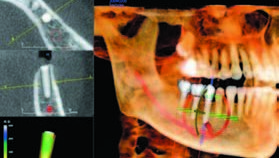

三维图像不仅为牙医提供手术前的准备,他们帮助医生教育患者,与患者进行良好的沟通,尤其是特殊的例如需要植骨的种植前期沟通。 我可以用从KaVo 3D eXam得来的数据结合第三方软件,例如InVivo5™ ,SimPlant®, NobelGuide™ 等来制定精确的治疗计划,以及提供手术导板达到更精确地种植效果。

因为我在自己的诊所就可以完成扫描,相比于一些影像拍摄中心或一些综合医院的更高辐射的医学CT扫描,病人和我都将受益于便利性和时效性。我也可以通过KaVo 3D eXam的专利准直器调节技术,减小投照区域只获取需要的区域以避免病人过度辐射,特别是术后扫描可以让我确认是否术后是否愈合和成功,比如植骨和上颌窦提升。

锥束成像提供的 “手术视角” 已经成为了我种植治疗的重要部分。我也相信锥束CT扫描不能过多地被用于“标准治疗”,而应该是“恰当治疗”,这一点很重要。基于个体独特的生活方式和特殊口腔问题来提供合适的治疗是牙医的责任。我使用锥束成像为特定病人辨别最好的治疗过程,例如是否该采用种植还是传统桥。